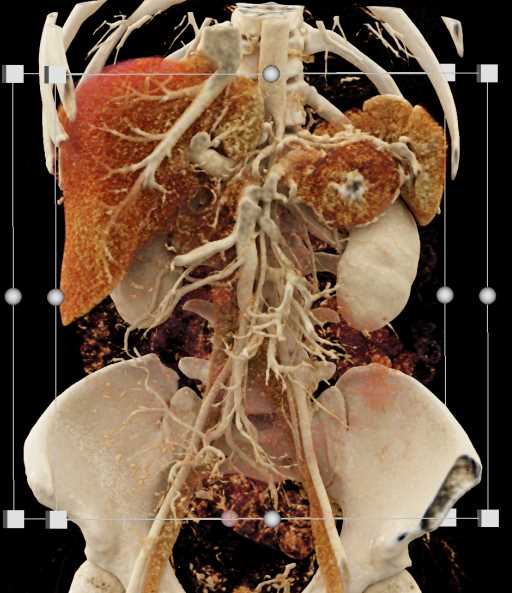

Neuroendocrine Tumor Pancreas